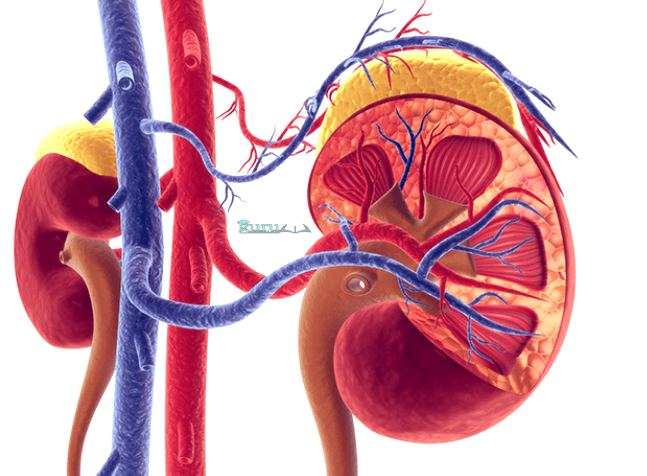

2. Ginjal

Ginjal merupakan suatu komponen utama dari sebuah sistem ekskresi terhadap manusia, yakni urin. Manusia mempunyai sebuah sepasang ginjal setinggi kurang lebih 10 cm. Lokasi ginjal berada di rongga perut kiri dan kanan – vertebra.

Ginjal memiliki sebuah fungsi sebagai menyaring sisa metabolisme dari darah, menjaga keseimbangan terhadap cairan tubuh, mengeluarkan gula darah di atas kadar normal dan mengatur keseimbangan basa, asam, dan garam dalam tubuh.